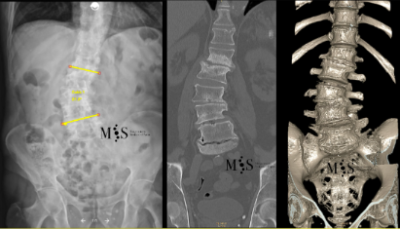

Scoliosis is a deformity/curving of the spine in the frontal plane. It can be congenital (present since birth) or degenerative (developed during the aging process). Progressive degeneration of the intervertebral disks (because of age, weight, activity, etc.) can lead to the spine to deform and curve in, ending up as a degenerative scoliosis, also called "de novo" because it is of "new" appearance in comparison to congenital scoliosis which has been present since birth.

Scoliosis lead to a curved back with the patient having problems walking with a straight back, and it can lead to an intense back pain. The spinal deformity and curving can lead to an impingement of the nerve roots which can cause radiating leg pain.

In these painful cases, surgery is indicated to (partially) correct the deformity and mainly to reduce/eliminate the pain generated by the scoliosis. In the most severe scoliosis cases an osteotomy (chiseling of a vertebral bone) may be required to straighten up the spine and reduce its deformity.